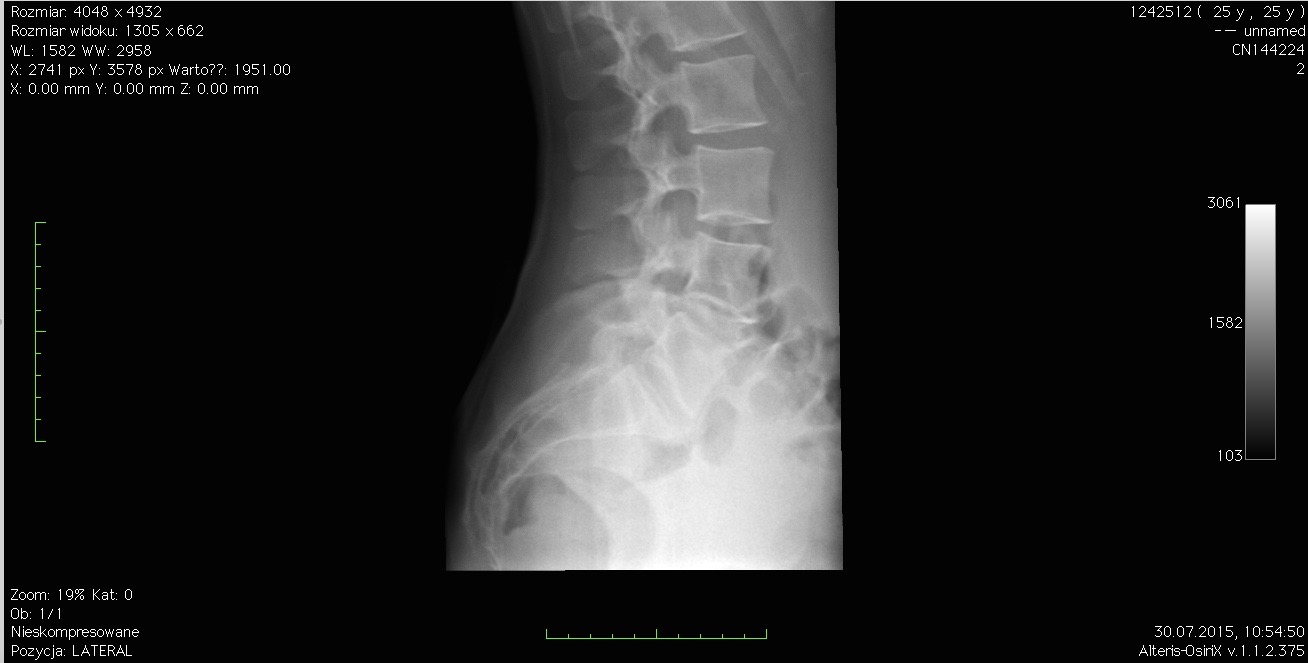

Kiedy przydatne jest wykonanie zdjęcia rentgenowskiego (RTG)?

Potoczny rentgen to podstawowe badanie dodatkowe w ortopedii, choć jego możliwości są przez pacjentów bardzo często przeceniane. Diagnostykę RTG stosuje się głównie w celu wykluczenia urazów tkanki kostnej, ponieważ praktycznie tylko kości są na tego rodzaju zdjęciach widoczne. Rentgen absolutnie nie nadaje się do oceny tkanek miękkich typu urazy więzadeł, mięśni czy otaczające je struktury nie będących elementami kostnymi.

Dlaczego właśnie to badanie wykonuje się najczęściej? Ponieważ niewykryte złamanie lub pęknięcie kości jest bardzo groźne i może prowadzić do bardzo nieprzyjemnych konsekwencji w postaci zagrożenia trwałej utraty zdrowia, a nawet życia. Wykonanie rentgena nie daje gwarancji, iż inne tkanki nie są uszkodzone, jednak daje względną pewność, że uraz nie jest na tyle poważny, iż konieczna jest natychmiastowa interwencja chirurgiczna lub pobyt w szpitalu.

Zdjęcie rentgenowskie jest przydatne głównie do oceny uszkodzeń i patologii tkanki kostnej.